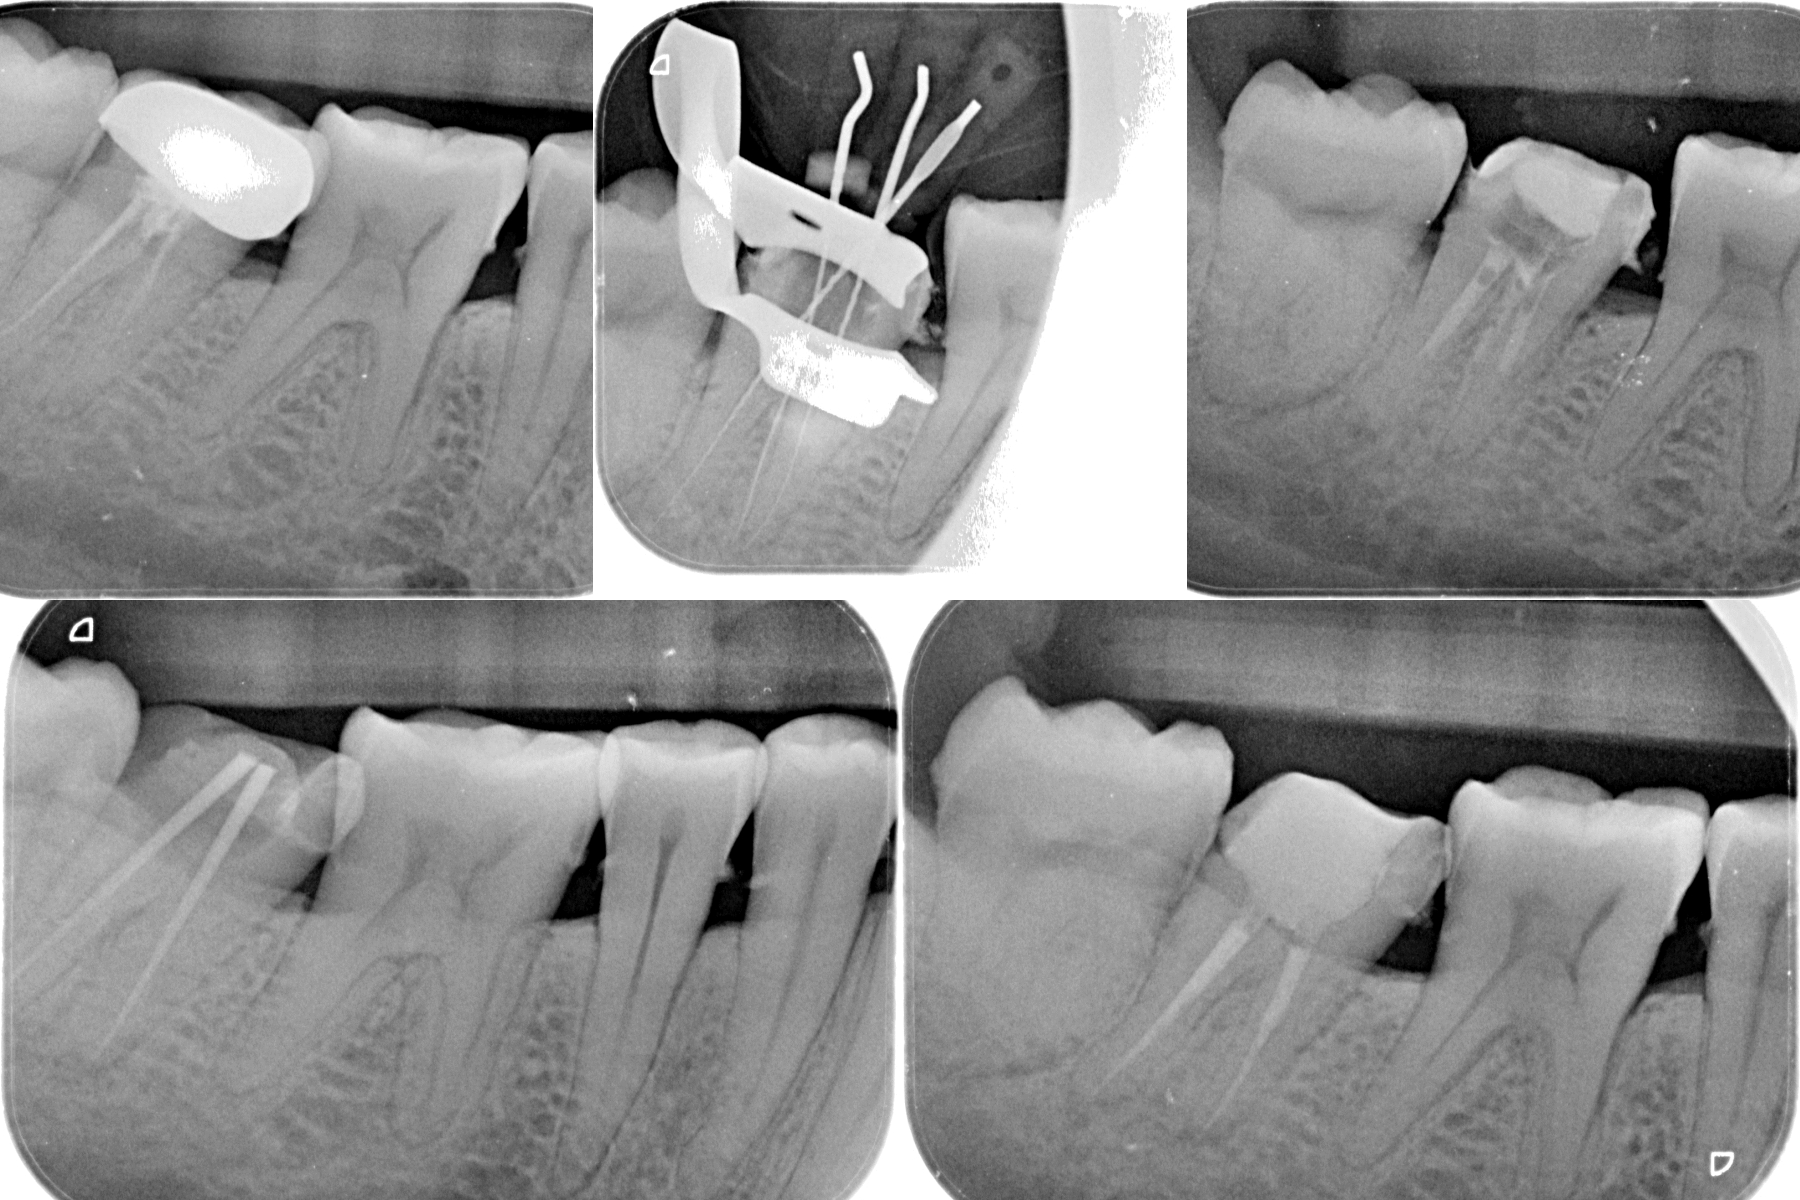

Pt 50 YOF presented with dislodged crown and severe pain in the recently RCT done #31. Started Re-treatment, after cleaning the chamber saw three orifices and finished the canals preparation, but was not sure of the distolinugal. I did not diagnose perforation as there was no bleeding nor patient complained of any pain during the preparation. Later Scan confirmed perforation and was sealed with fiber reinforced composite.